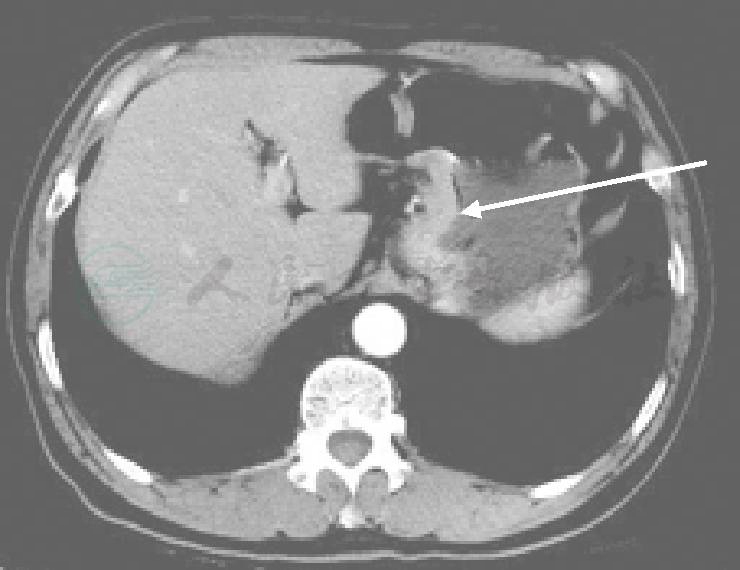

图8 CT增强

右肾低密度见不均匀强化(箭头)